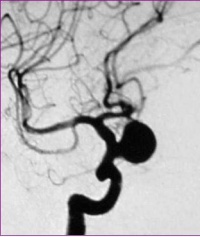

颅内动脉瘤多因脑动脉管壁局部的先天性缺陷和腔内压力增高的基础上引起。高血压、脑动脉硬化、血管炎与动脉瘤的发生与发展有关。脑动脉瘤多见于脑底动脉分叉之处。按其发病部位,4/5位于脑底动脉环前半,以颈内动脉、后交通动脉、前交通动脉者多见;脑底动脉环后半者约占1/5,发生于椎基底动脉、大脑后动脉及其分支。症状:动脉瘤破裂时,常有前驱症状如头痛,继之发生出血症状,表现为剧烈头痛、烦躁、恶心呕吐等脑膜刺激征,随之出现颅内压增高。可伴有意识障碍和相应部位的神经定位症状。动脉瘤出血形成较大血肿者,病情多急剧恶化,出现脑疝危象。据统计动脉瘤第一次破裂后,死亡率高达30~40%,其中半数在发病后48小时内死亡,存活的病例,1/3可发生再次出血。检查:脑血管造影是最确切的辅助诊断方法,应行全脑血管造影。CT扫描有时可以显示出动脉瘤病灶。MRI检查不仅可显示出动脉瘤,有时尚可见到附壁血栓。一旦诊断为脑动脉瘤,应采取手术治疗,以求根治,避免大出血危险。采用开颅直接处理动脉瘤的手术方法。尚可采用动脉内栓塞治疗。

3.脑血管造影是确诊颅内动脉瘤必须的检查方法,对判明动脉瘤的准确位置、形态、内径、数目、血管痉挛和确定手术方案都十分重要。DSA更为清晰。,经股动脉插管全脑血管造影,可避免遗漏多发动脉瘤。病情在三级以下,脑血管造影应及早进行,三级和三级以上病人可待病情稳定后,再行造影检查。及早造影明确诊断,尽快手术夹闭动脉瘤,可以防止动脉瘤再次破裂出血。首次造影阴性,可能因脑血管痉挛而动脉瘤未显影,高度怀疑动脉瘤者,应在3个月后重复造影。